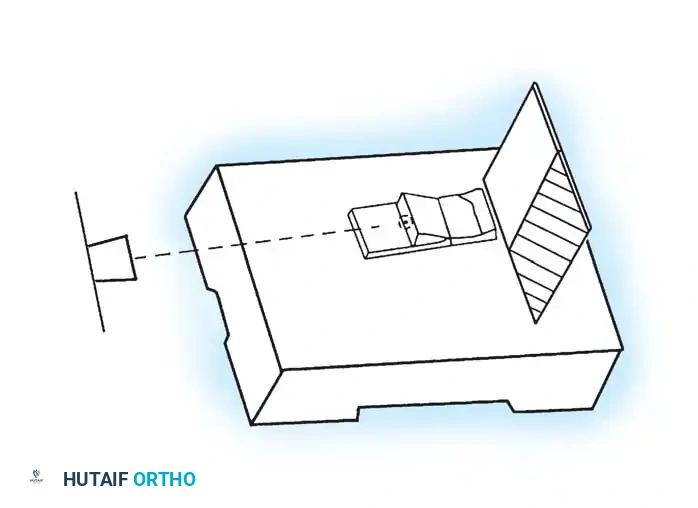

Roentgen beam

Platform Sesamoid view stand

Cassette

Slot for cassette

40 inches from x-ray source to cassette and 15° from “vertical”